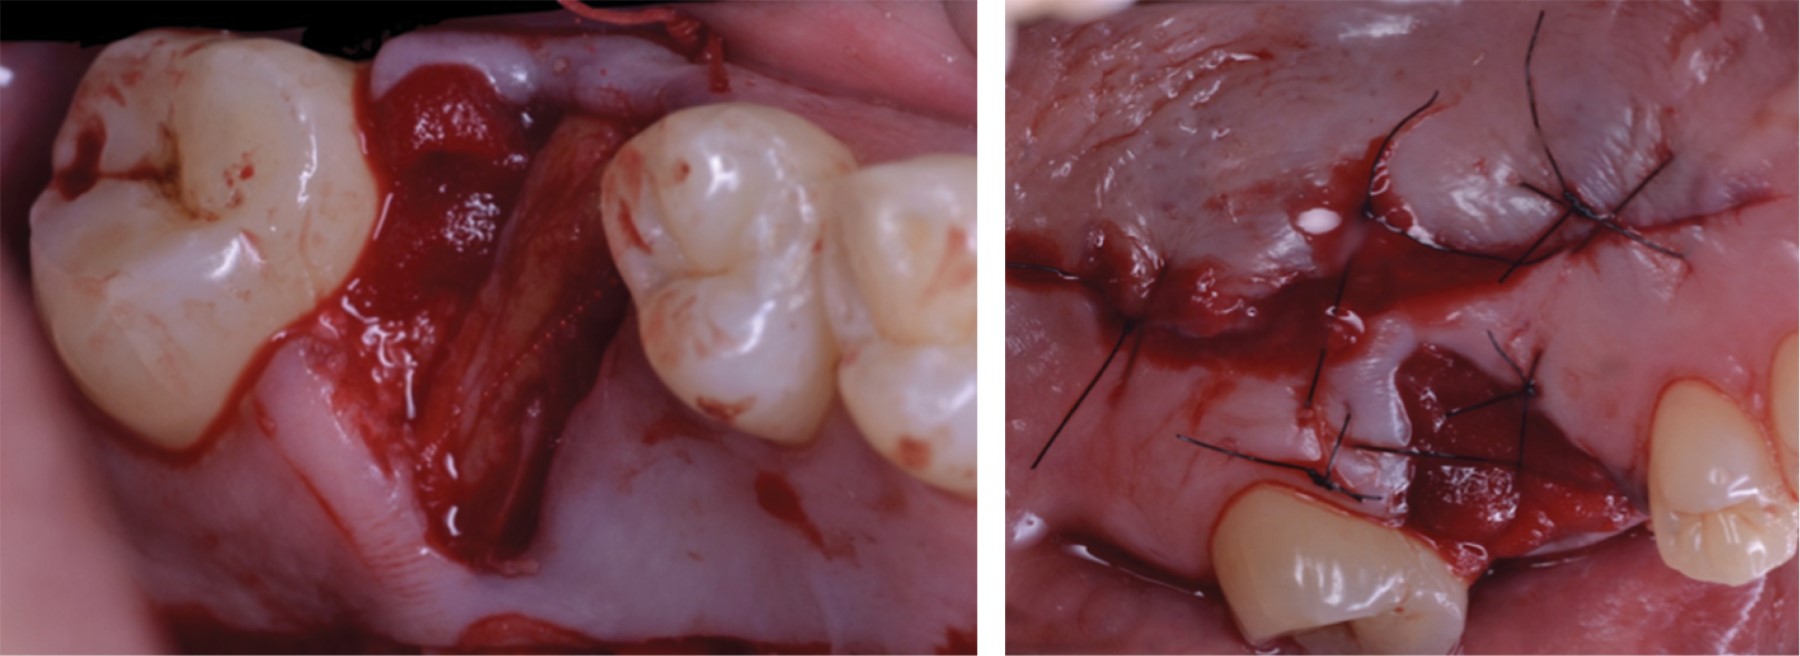

Se realizó fase higiénica periodontal (detartraje y profilaxis). Se citó al paciente para extracción y se llevó a cabo ARP; se colocó una matriz colágena (MatrixDerm Tape) en los ápices del alveolo y se colocó injerto óseo de tipo aloinjerto2,9 (Allograft-LifeNet Health) (Figura 3). Se seleccionó la técnica de colgajo pediculado de paladar de tejido conectivo subepitelial para cubrir el alveolo.9

Se realizó una incisión paramarginal palatina, en promedio a dos milímetros apical de la recesión palatina (margen gingival) desde la porción distal del segundo molar superior derecho hasta la porción mesial del segundo premolar superior derecho, y una descarga distal (diseño descrito por Liu y colegas.)22 y se reflejó un colgajo mucoperióstico para obtener acceso al tejido conectivo donante (Figura 4).9

Después se realizó una incisión aguda del tejido subepitelial, paralela a la primera incisión para obtener un injerto de tejido conectivo (se buscó mantener un grosor constante de dos milímetros,15 dejándolo pediculado en la región posterior) (Figura 5). Se colocó una matriz colágena sobre el injerto óseo, se elevó el colgajo de tejido conectivo subepitelial, se tunelizó por debajo de la porción palatina y se rotó para cubrir el defecto (Figura 6).

La base del pedículo fue más ancha que la porción coronal para asegurar la adecuada vascularización.15 El colgajo pediculado se suturó en la zona vestibular con un punto simple (vicryl 4-0); se colocó otra matriz colágena sobre el injerto pediculado cubriendo el alveolo y se instaló otra matriz colágena dentro de la zona donante (por debajo del epitelio) y se realizó una sutura (nilón 4-0) en X para fijar la matriz (Figura 6).

Figura 3

Figura 4

Figura 5